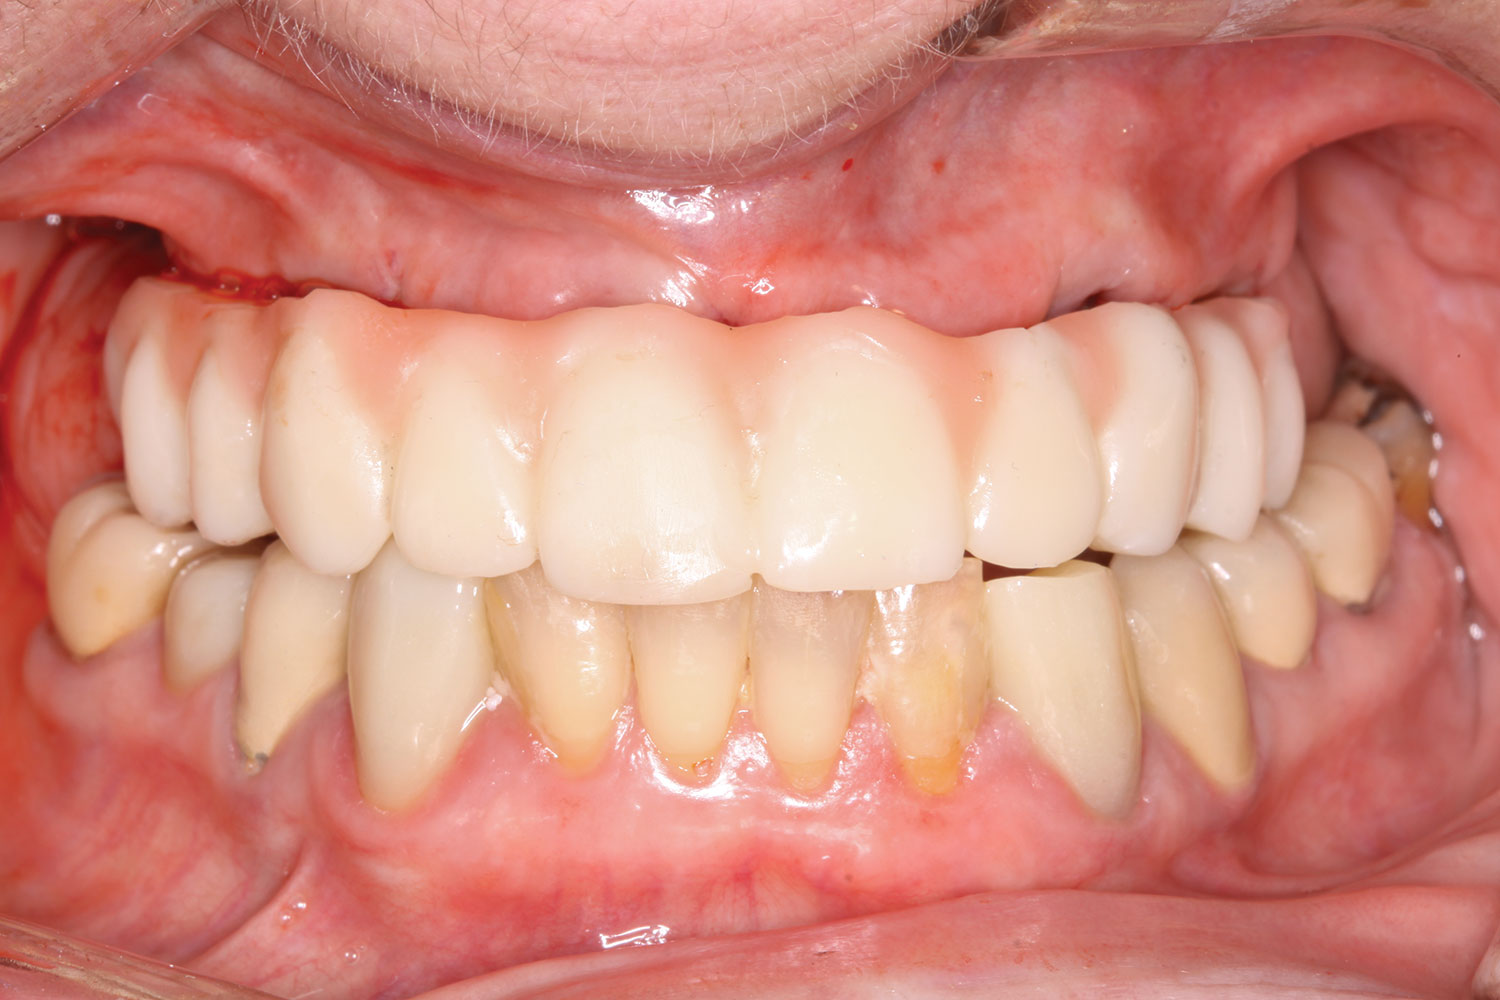

Fig 18. Implants and provisional maxillary prosthesis in place, the same day as surgery.

Figure 18

The completed provisional prosthesis was then screwed onto the multi-unit abutments with titanium screws and torqued to 20 Ncm. Screw-access holes were filled, and no occlusal adjustment was necessary. The fit of the prosthesis was precise and stable, and the patient's phonetics were ideal. The patient was overwhelmed by the significant esthetic improvement with this set of teeth in place (Figure 6 through Figure 8).

The prosthesis fit precisely on the multi-unit abutments, and multi-unit screws were used to secure the prosthesis in place at 20 Ncm (Figure 18 through Figure 20). The screw-access holes were filled, and the patient was instructed on dietary restrictions and adherence to a soft diet. Instructions for oral hygiene were given, and the patient was advised to use a water flosser daily. Analgesics included ibuprofen 800 mg, and for antibiotics, amoxicillin 500 mg three times a day was prescribed.